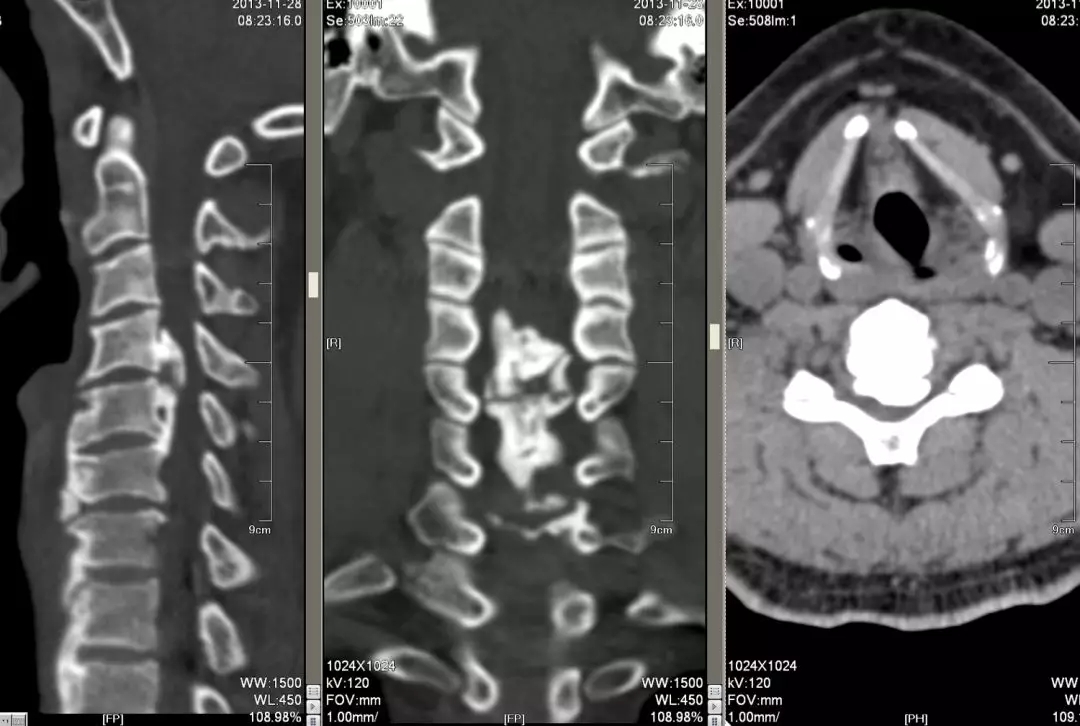

这是同一个病的ct,我们可以看到很明显的后纵韧带的骨化,